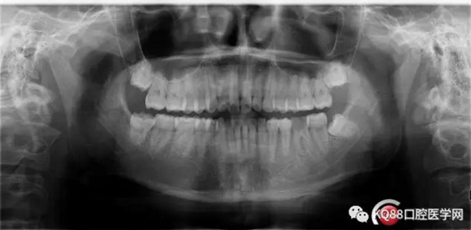

X-ray:36根尖云霧狀低密度影,根分叉未見異常。

診斷:36慢性增生性牙髓炎。